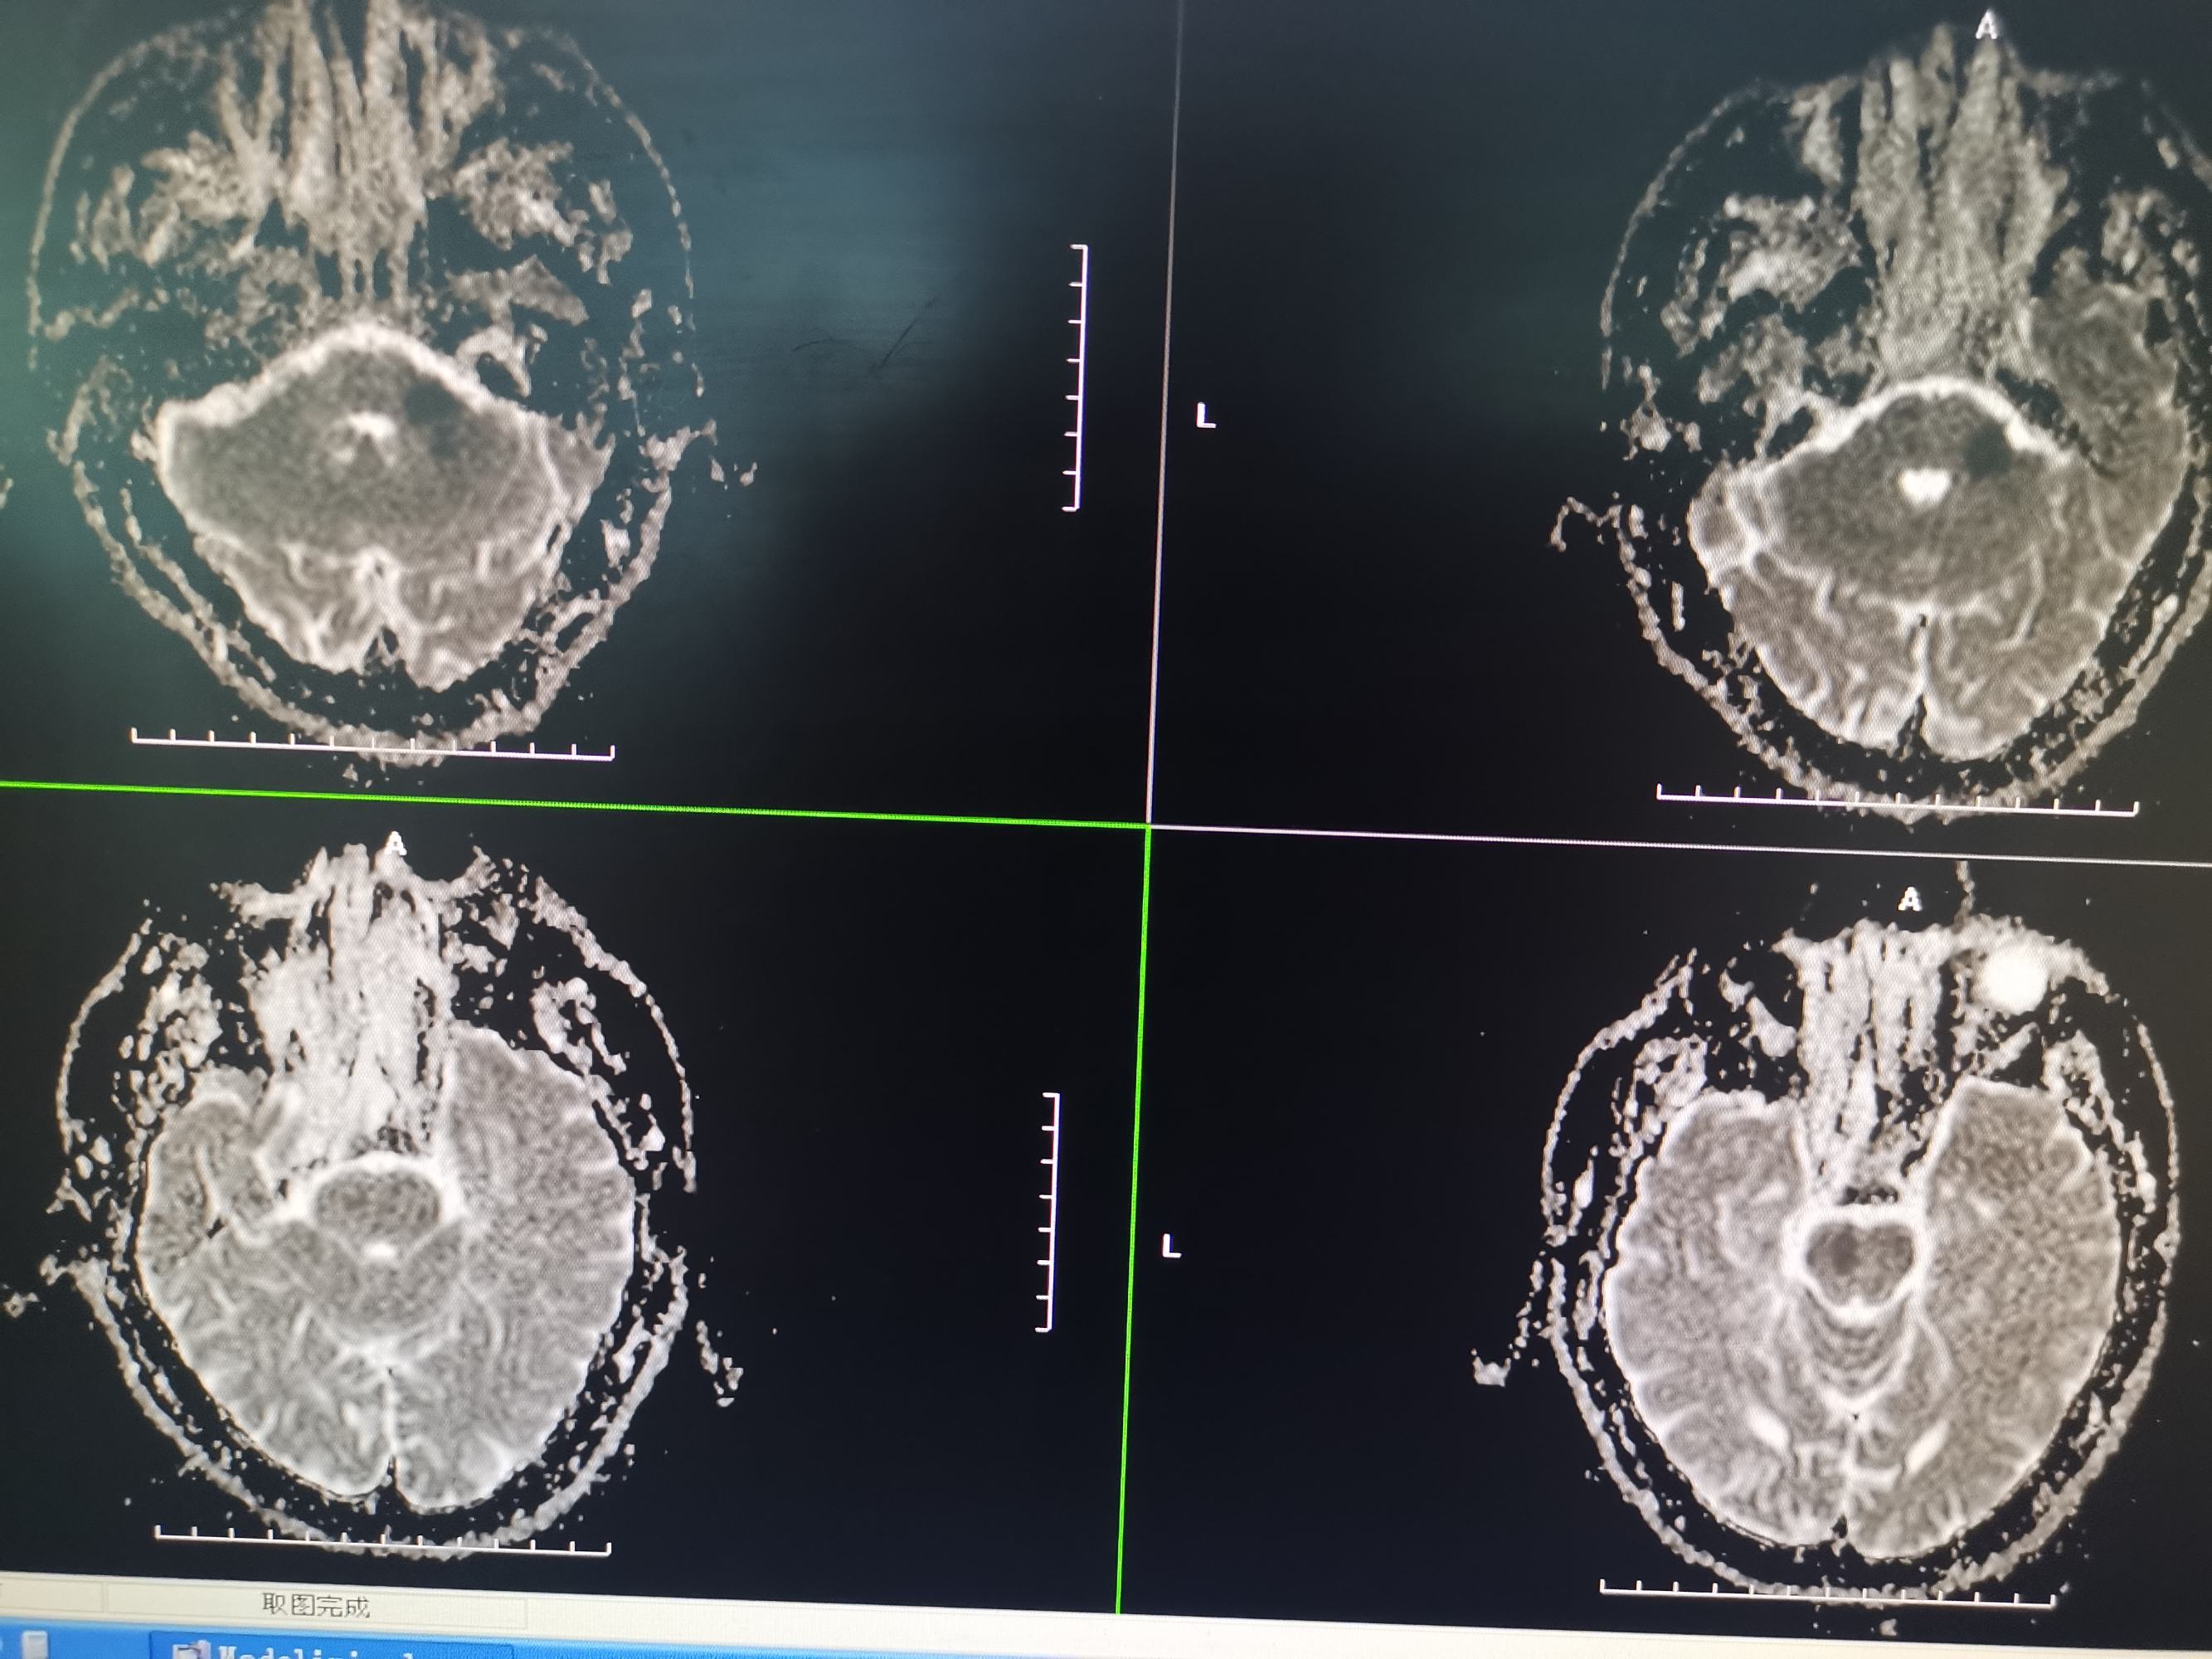

入院MR

男性,56岁,突发意识嗜睡,言语不能,吞咽困难,右侧肢体偏瘫于8月7日收住院。入院后急诊给予阿替普酶静脉溶栓,溶栓后造影显示双侧椎动脉闭塞,后交通未开放,仅右侧椎动脉有一穿支向基底动脉少量供血,考虑为原位狭窄后急性闭塞。核磁显示脑干及小脑多发急性梗死灶,拟双抗3周后行再通治疗。给予阿司匹林100mg及氯吡格雷75mg双抗3周后患者吸入性肺炎并反复消化道出血,停双抗治疗给予抗炎、抑酸药物治疗后感染控制,消化道出血停止,查血栓弹力图后重启双抗治疗一周,病情稳定,于今日在全麻下行左侧椎动脉再通术,手术顺利,详细情况如下